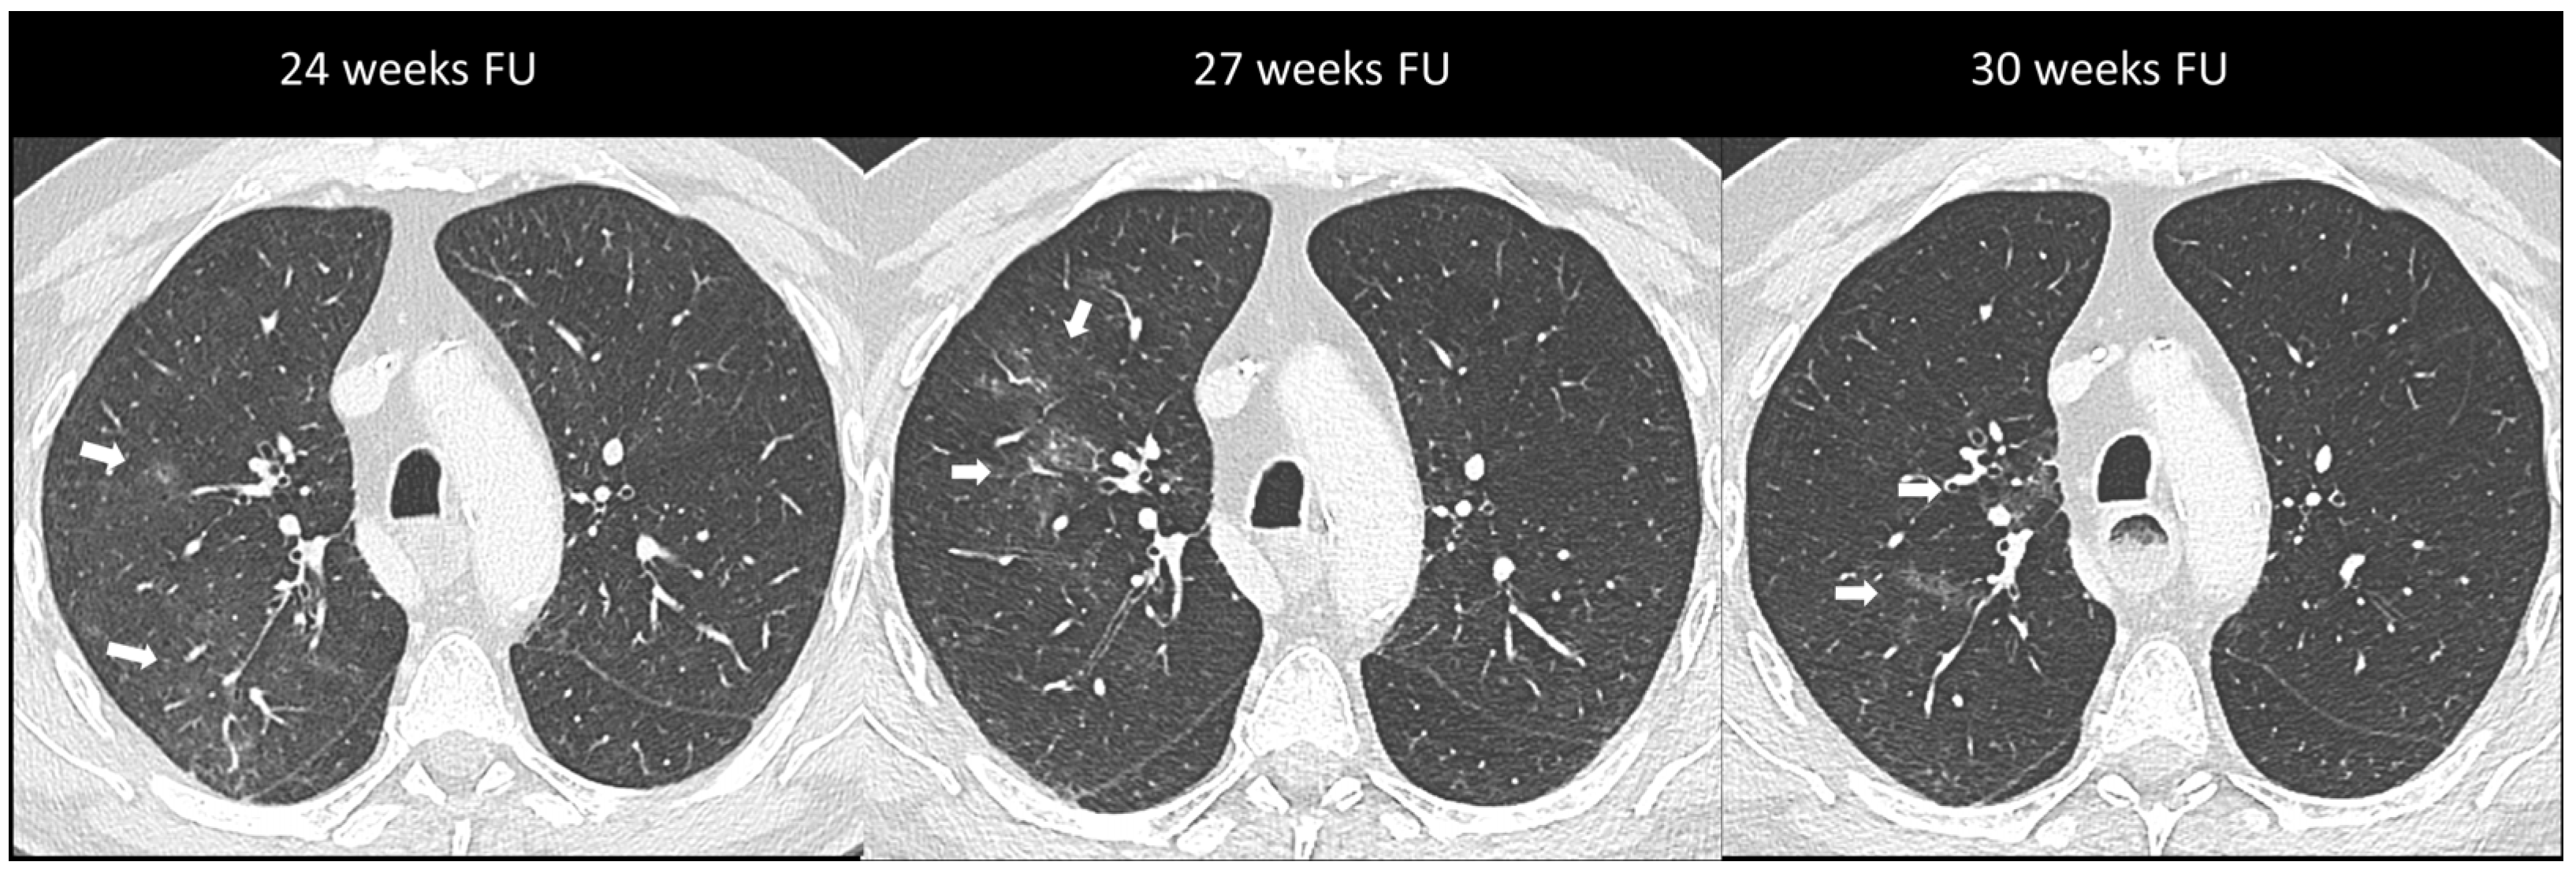

2.2.1. Ir-Pneumonitis

- Pozzessere, C.; Lazor, R.; Jumeau, R.; Peters, S.; Prior, J.O.; Beigelman-Aubry, C. Imaging Features of Pulmonary Immune-related Adverse Events. J. Thorac. Oncol. 2021, 16, 1449–1460. [Google Scholar] [CrossRef]

- Nishino, M. Imaging of Oncologic Treatment–Related Pneumonitis: A Focused Review on Emerging Issues of Immune Checkpoint Inhibitor Pneumonitis, from the AJR Special Series on Inflammation. Am. J. Roentgenol. 2022, 218, 19–27. [Google Scholar] [CrossRef]

- Johkoh, T.; Lee, K.S.; Nishino, M.; Travis, W.D.; Ryu, J.H.; Lee, H.Y.; Ryerson, C.J.; Franquet, T.; Bankier, A.A.; Brown, K.K.; et al. Chest CT Diagnosis and Clinical Management of Drug-related Pneumonitis in Patients Receiving Molecular Targeting Agents and Immune Checkpoint Inhibitors: A Position Paper from the Fleischner Society. Radiology 2021, 298, 550–566. [Google Scholar] [CrossRef]

| Pneumonitis | OP | Multifocal, patchy, consolidations or GGOs with peribronchovascular and/or subpleural distribution | Migratory on a subsequent scan | Radiation Pneumonitis Infectious pneumonia Tumor progression |